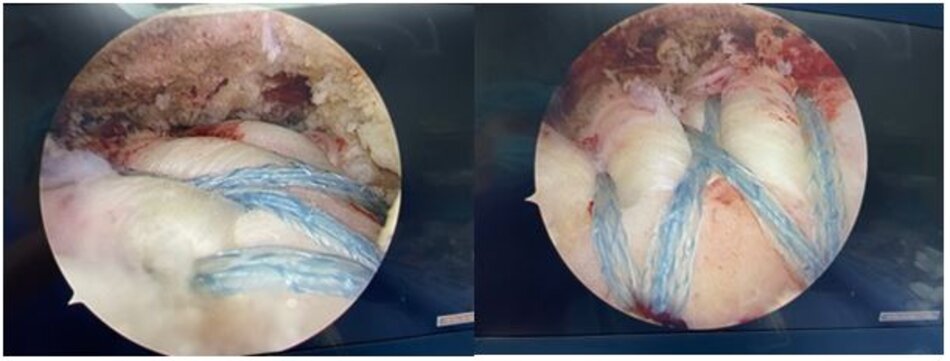

Gân trên gai sau khi được tạo hình khâu lại vào điểm bám cũ